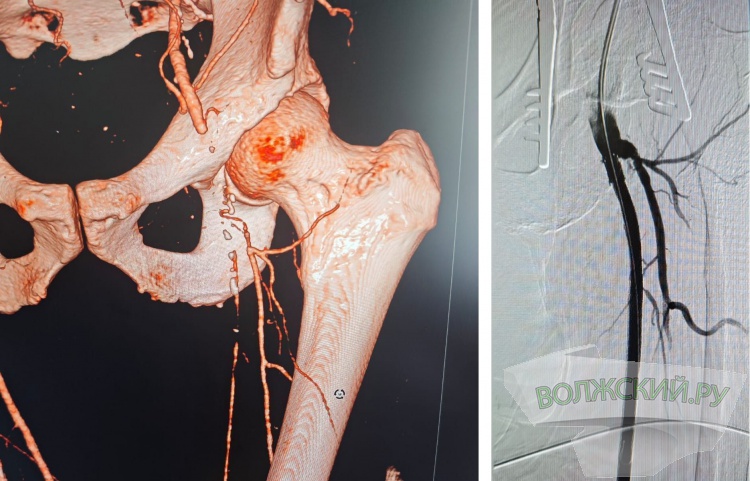

Как рассказали Волжский.ру в комитете здравоохранения, в областной клинической больнице №1 сердечно-сосудистые хирурги провели уже более двух десятков операций, где комбинируется техника открытой сосудистой хирургии и эндоваскулярной методики для восстановления кровообращения в нижних конечностях при различных заболеваниях. Так врачи удаляют бляшки или тромб из общей бедренной и глубокой артерии бедра с ее последующей пластикой и стентированием поверхностной бедренной артерии.

Такие операции «с одним наркозом» позволяют быстрее достигнуть нужного эффекта и уменьшить срок восстановления пациента, по сравнению с несколькими этапными операциями.